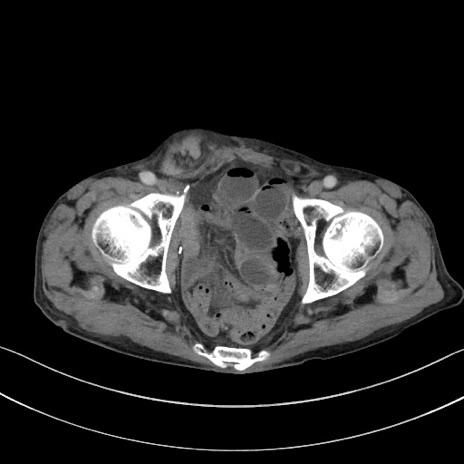

症例3(横断像)

【症例】 70歳代男性

【主訴】右鼠径部腫瘤、疼痛

【現病歴】本日朝より上記主訴あり、受診。

【既往歴】膀胱癌にて膀胱全摘、両側尿管皮膚瘻

【データ】WBC 5600、CRP 0.56